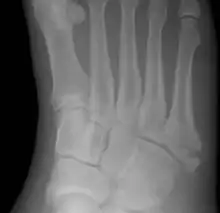

Jones fracture as seen on Xray

A Jones fracture is a broken bone in a specific part of the fifth metatarsal of the foot between the base and middle part[8] that is known for its high rate of delayed healing or nonunion.[4] It results in pain near the midportion of the foot on the outside.[2] There may also be bruising and difficulty walking.[3] Onset is generally sudden.[4]

Diagnosis

A person with a Jones fracture may not realize that a fracture has occurred. Diagnosis includes the palpation of an intact fibularis brevis tendon, and demonstration of local tenderness distal to the tuberosity of the fifth metatarsal, and localized over the shaft of the proximal metatarsal.

Diagnostic X-rays include anteroposterior, oblique, and lateral views and should be made with the foot in full flexion.